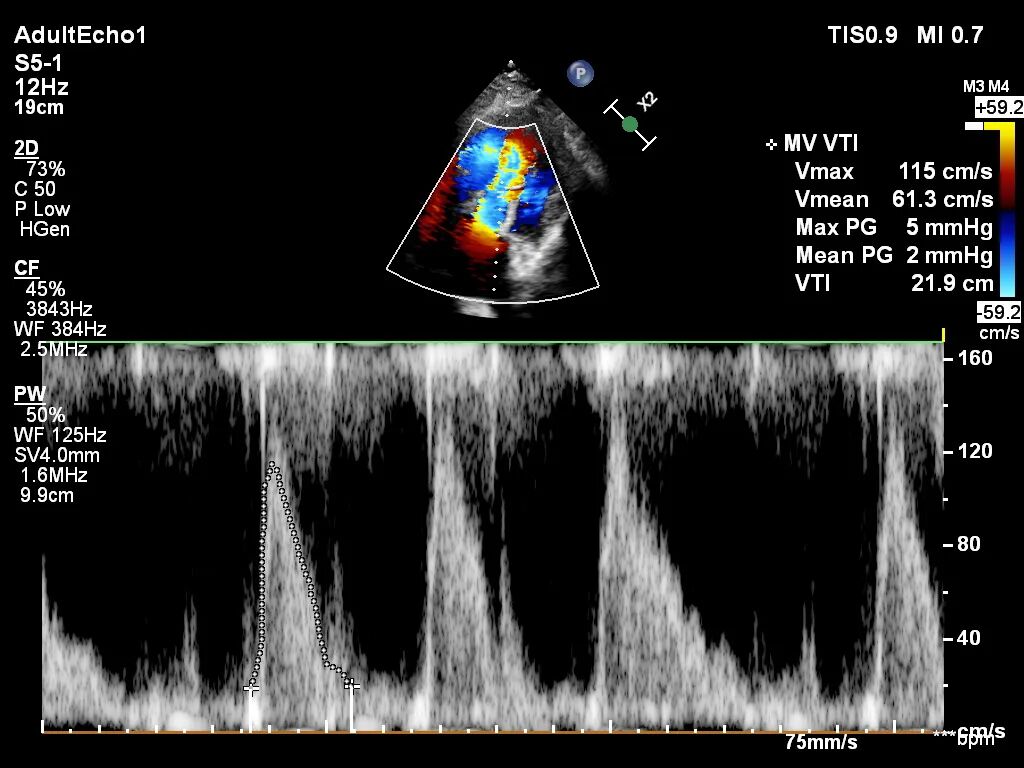

血流动力学

手术采用左侧第五肋间微创切口入路,超声引导下经心尖将导丝置入左房,送入瓣膜输送系统,经过一系列超声定位后逐渐释放瓣膜。确认瓣膜位置满意后撤出输送系统,瓣架恢复膨胀完全、锚定良好,人工二尖瓣瓣叶形态完好,无反流及无瓣周漏,人工二尖瓣峰值流速1.10m/s、平均压差2mmHg,峰值压差5mmHg,由连续多普勒据PHT估测面积约3.5cm²,左室流出道无梗阻,峰值流速0.76m/s。术中出血约100ml,无输血,术后患者安全返回监护室。

术后第2天患者出监护室,术后第4天拔管,术后第5天顺利出院。出院前心超显示:经导管二尖瓣人工瓣膜植入术后,人工瓣膜支架固定,形态未见异常,瓣叶开放不受限,瓣口由多普勒估测其开放峰值流速为1.15m/s,峰值压差5mmHg,平均跨瓣压差为2mmHg,由连续多普勒据PHT估测面积约2.93cm²,瓣叶关闭形态未见异常,彩色多普勒未测及二尖瓣反流及瓣周漏;左心室流出道通畅,流出道峰值流速0.93m/s。

出院时人工瓣膜开口面积

出院时人工瓣膜跨瓣压差